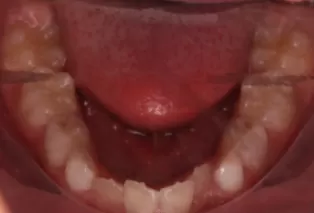

Intraoral photos